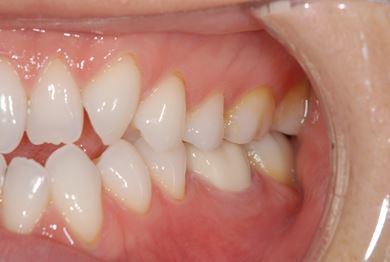

治療後

• 治療後